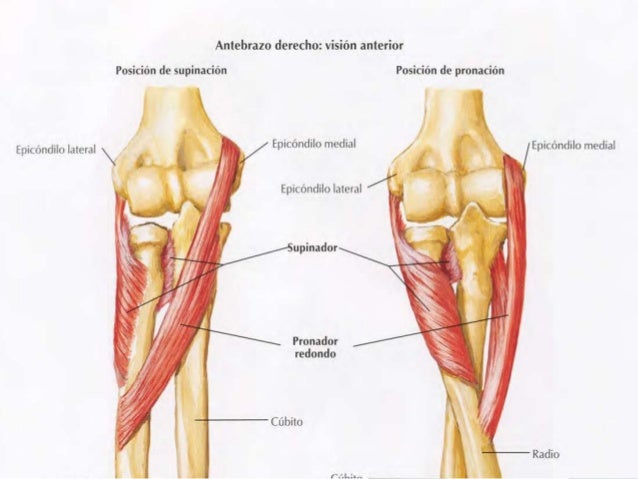

MÚSCULOS DE LA ARTICULACIÓN RADIOUNLAR

tenemos

PRONADORES

SUPINADORES